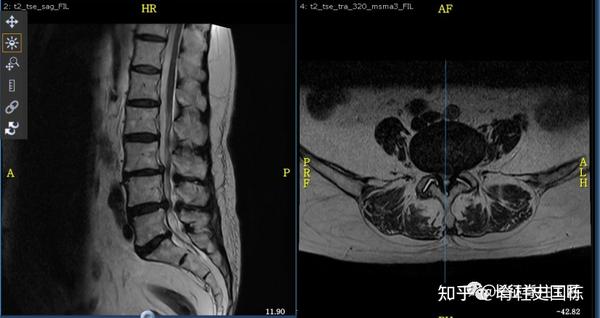

脊柱管狭窄症 Mri : 断面の脊柱管腔は純粋に客観的な評価となり,クモ膜 下腔の狭小化と術前の脊柱管狭窄症による症状の相関 表1 各椎間・撮影方法での脊柱管前後径比 l1/2椎間 l2/3椎間 l3/4椎間 腰椎mri 0.8660.830.679